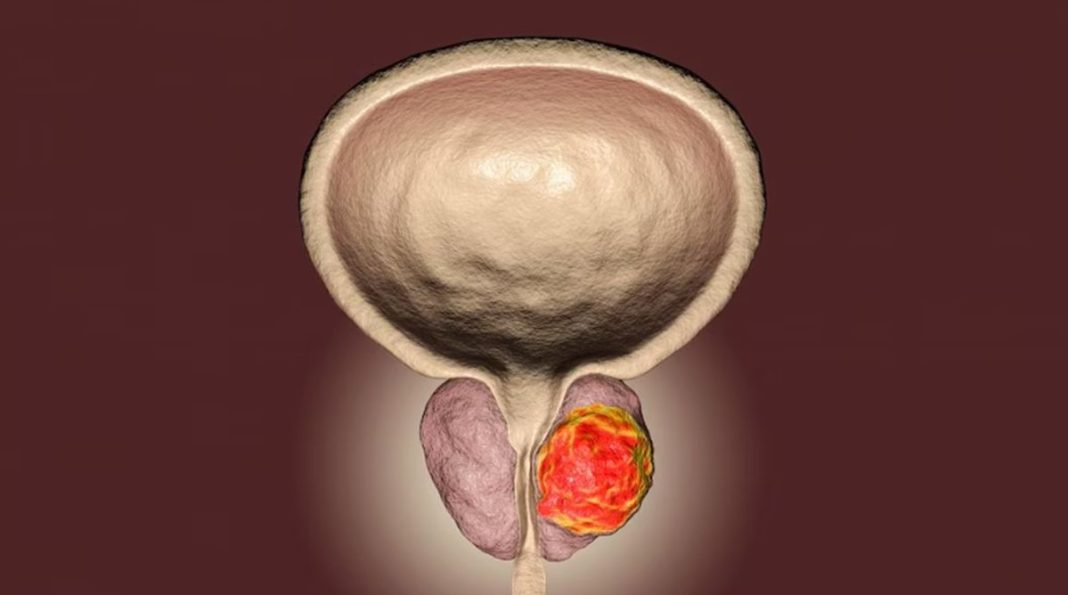

Η καλοήθης υπερπλασία του προστάτη είναι η πιο συχνή πάθηση στους μεσήλικες και ηλικιωμένους άνδρες. Με την αύξηση της ηλικίας του άνδρα ο προστάτης μεγαλώνει σε μέγεθος και δημιουργεί προβλήματα στην ομαλή έξοδο των ούρων. Η αντιμετώπιση του προβλήματος της υπερπλασίας του προστάτη παρουσιάσει σημαντική εξέλιξη τα τελευταία χρόνια και πλέον, αντιμετωπίζεται με την προηγμένη τεχνική MiLEP, η οποία αποτελεί μετεξέλιξη της τεχνικής HoLEP.

Oι άνδρες στην πορεία της ζωής τους αντιλαμβάνονται αλλαγές στην ούρηση. Αυτό οφείλεται στην ανάπτυξη αδενώματος εντός του προστάτη αδένα. Στις συντριπτικά περισσότερες περιπτώσεις πρόκειται για καλοήθη ιστό χωρίς καμία λειτουργική συνεισφορά. Το μόνο που κάνει είναι να εμποδίζει την ελεύθερη ροή των ούρων, εκδηλώνοντας γνώριμα στους μεσήλικες άνδρες συμπτώματα όπως μείωση της ευκολίας ροής, συχνουρία, νυκτουρία και επιτακτική ανάγκη ούρησης, ακράτεια, ακόμη και αδυναμία ούρησης. Αυτά, ξεκινώντας από απλή ενόχληση, εξελίσσονται σε μείζον πρόβλημα που θέλει ιατρική λύση.

H Ιατρική δεν έπαψε να ερευνά μεθόδους περισσότερο ακίνδυνης και λιγότερο τραυματικής θεραπείας της καλοήθους κατάστασης. Η πρόοδος αυτή οδήγησε στην ολική εκπυρήνιση του αδενώματος μέσω Holmium Laser (HoLEP) που την τελευταία δεκαετία αποτελεί χρυσό κανόνα στην αντιμετώπιση της καλοήθους υπερπλασίας προστάτη, καθώς είναι αναίμακτη ως διαδικασία. Έτσι, οι ασθενείς που λαμβάνουν αντιπηκτική αγωγή για σοβαρούς λόγους, της οποίας η διακοπή θα θέσει τη ζωή τους σε κίνδυνο, πλέον μπορούν να χειρουργηθούν! Επίσης, προσφέρει οριστική λύση και όχι μερική, όπως η ευρέως διαδεδομένη διουρηθρική (TURis) αφαίρεση του αδενώματος, αφού δεν καταλείπεται υπολειμματικός ιστός που μπορεί να μεγαλώσει στο μέλλον. Έτσι, η παλιά συμβουλή που λάμβαναν οι χειρουργημένοι ότι θα ήταν εντάξει για 7-10 χρόνια δεν ισχύει πια. Μετά τη HoLEP ο άνδρας δεν αντιμετωπίζει ξανά πρόβλημα με την ούρηση!

Η αντιμετώπιση ενός συχνού και διαδεδομένου προβλήματος του άνδρα εισέρχεται σε νέα εποχή. Η laser εκπυρήνιση προστάτη HoLEP δεν περιορίζεται από τον ογκώδη εξοπλισμό ρεύματος της παλαιότερης διουρηθρικής εκτομής γνωστής ως TURP/TURis. Το φως, λόγω της φύσης του, εισέρχεται διά λεπτότατων εργαλείων στον στόχο, αλλάζοντας επαναστατικά την καταξιωμένη HoLEP σε μια νέα εκδοχή. Αυτή η νέα εκδοχή διαφέρει τόσο ριζικά από την παλιά που αυτοδικαίως αποκτά διεθνώς το νέο όνομα MiLEP. Μετά την ολοκλήρωση κλινικών μελετών που αποδεικνύουν τα πλεονεκτήματα έναντι της HoLEP, έχει υιοθετηθεί ήδη ως η επέμβαση εκλογής για αντιμετώπιση καλοήθους υπερπλασίας προστάτη παγκοσμίως σε εξειδικευμένα κέντρα όπου δραστηριοποιούνται έμπειρες ουρολογικές ομάδες όπως η δική μας.

Δεδομένου ότι η επέμβαση γίνεται μέσω της ανδρικής ουρήθρας, το μέγεθος του ενδοσκοπικού εργαλείου που εισάγεται σε αυτήν έχει σημασία – εδώ είναι κατά 30% μικρότερο. Όσο λεπτότερο τόσο «φιλικότερο» με την ευαίσθητη ουρήθρα, οπότε έχουμε αποφυγή τραύματος, άρα ταχύτατη αποκατάσταση, με λεπτότερο και ως εκ τούτου όχι δυσάρεστο ουροκαθετήρα. Επίσης, μεγαλύτερη ακρίβεια εντός του χειρουργικού πεδίου. Μπορούμε να κατευθύνουμε το ισχυρό 150 watts laser με ευέλικτο και ακριβή τρόπο, εξασφαλίζοντας ιδανικό διαχωρισμό μεταξύ φυσιολογικού και παθολογικού ιστού. Επιτυγχάνουμε, τελικά, βραχύτερο χρόνο επέμβασης.